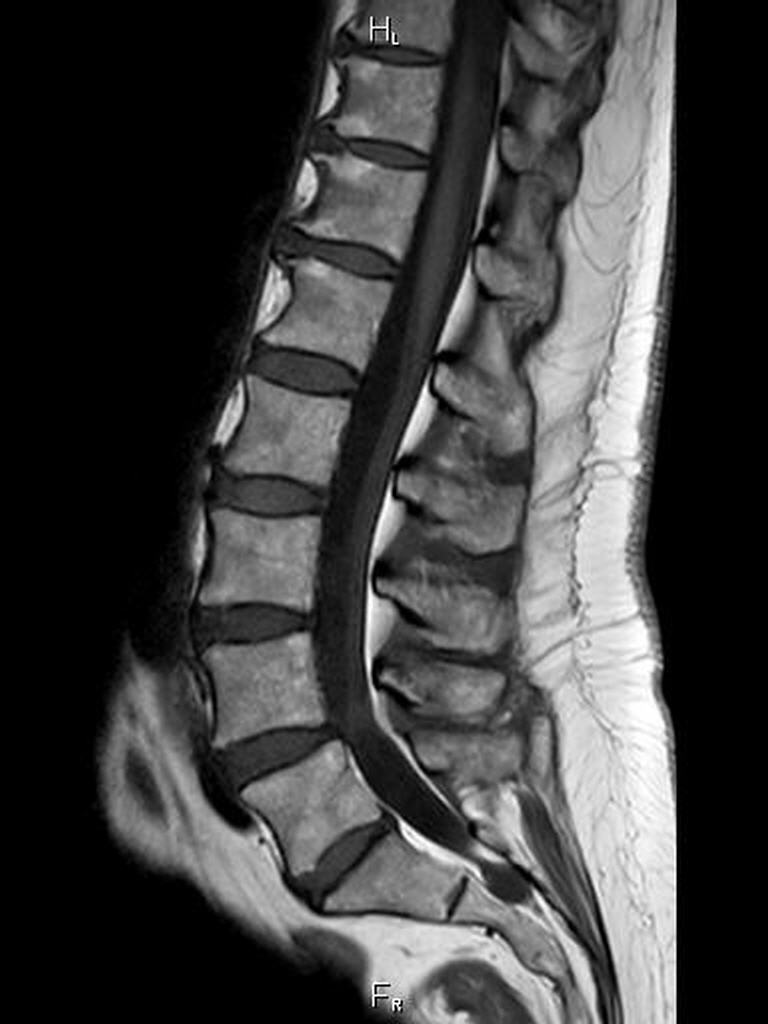

- Wirbelsäulendiagnostik